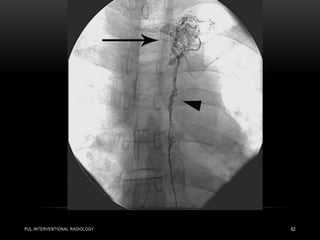

• Pulmonary angiography in a 57-year-old woman in shock from

acute bilateral massive PE. Initial right (a) and left

(b) pulmonary angiograms show near-complete obstruction.

Pulmonary artery pressure was 73/18 mm Hg. Final right (c) and

left

(d) images after suction thrombectomy and catheter-directed

thrombolytic agent injection into each main descending

pulmonary

artery. Pulmonary artery pressure was reduced to 36/16 mm Hg.

(Images courtesy of Daniel Y. Sze.)